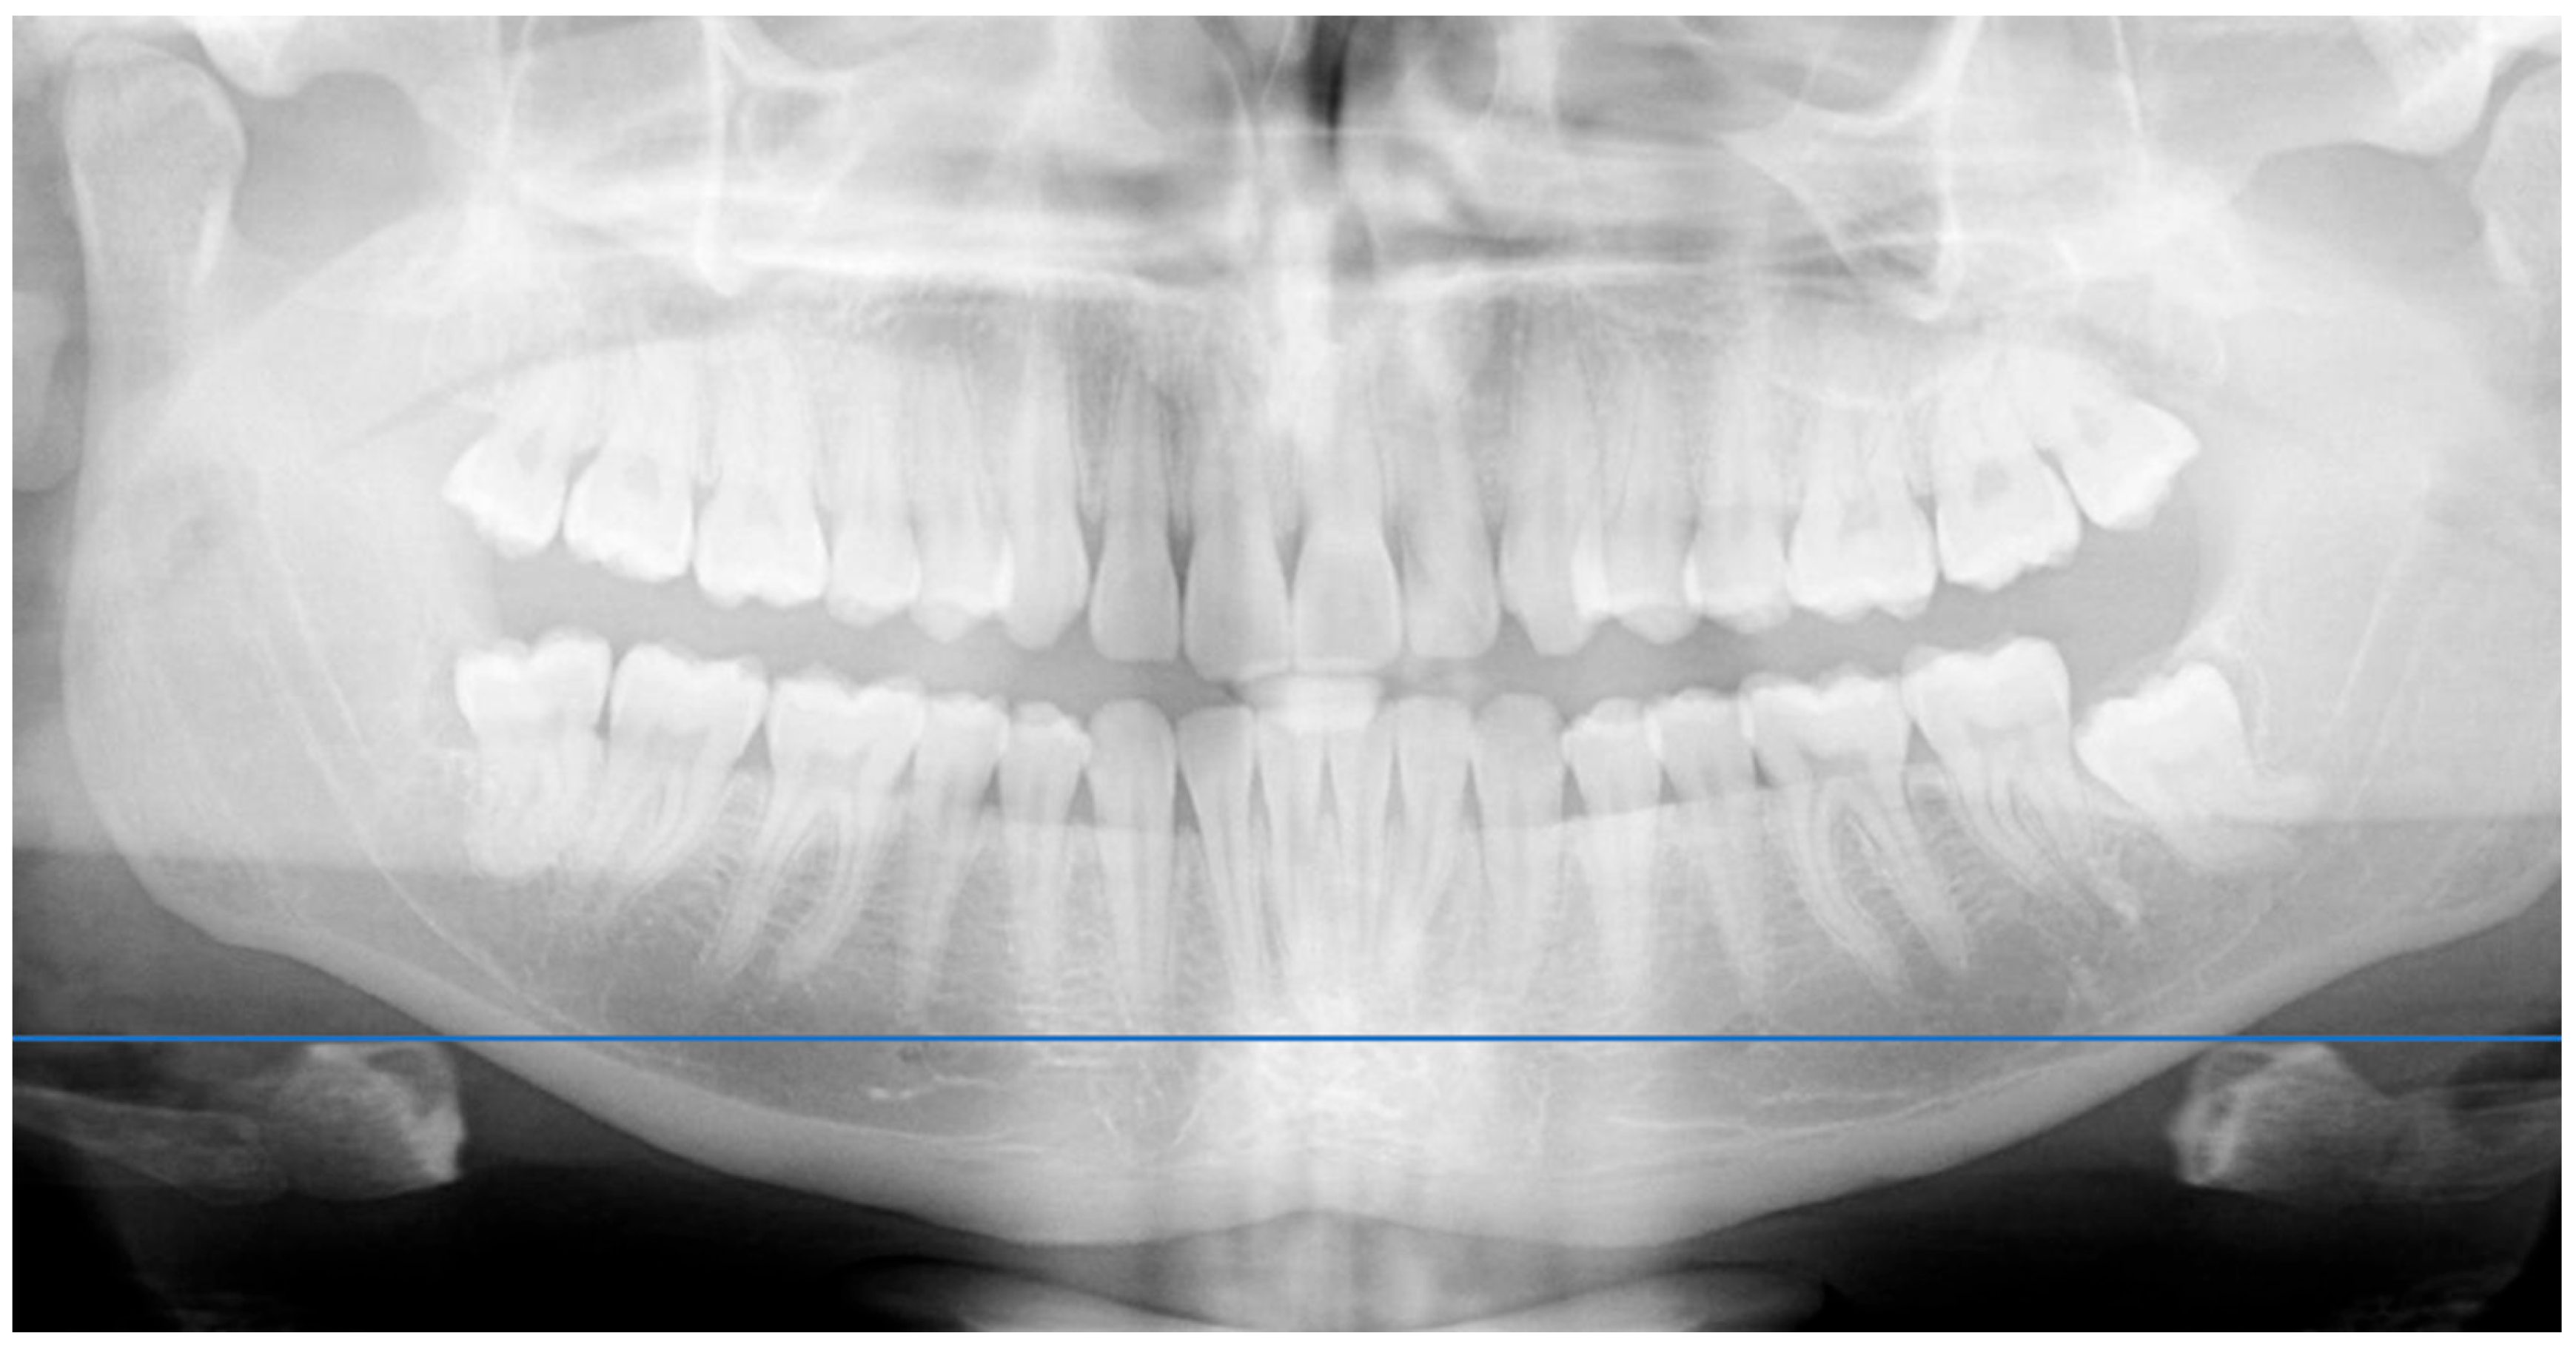

• Radiographic Analysis: A panoramic radiograph was obtained for each participant. A horizontal line was drawn across the hyoid bone, and vertical distances were measured from the upper border of the hyoid to the antegonial notch on each side using a digital ruler overlay (Figure 2). Distances were measured digitally from the most superior point of the hyoid body to the antegonial notch bilaterally, using an on-screen ruler calibrated at the same scale.

Figure 2. Horizontal reference line drawn for comparative analysis of hyoid bone position.